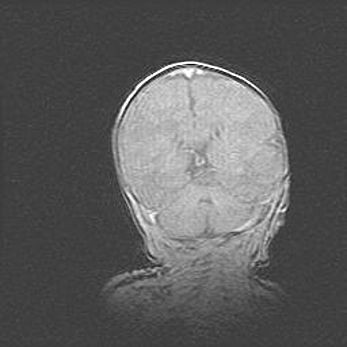

Церебральная ишемия II.

Возраст: 5 дней

Вес: 3400 г

Пол: женский

Окружность головы: 35 см

Срок гестации: 39 недель

Церебральная ишемия – это заболевание, характеризующееся недостаточностью (гипоксией) либо полным прекращением (аноксией) снабжения мозга кислородом по причине закупорки одного или нескольких сосудов. Это приводит к  что метаболическим расстройствам различной степени тяжести в тканях головного мозга, развитию коагуляционных некрозов и гибели нейронов.